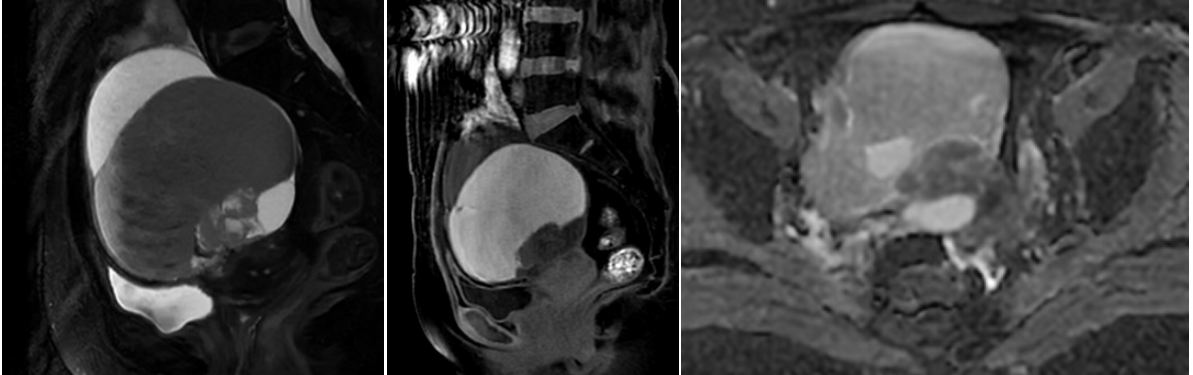

OCCC以囊实性多见,且大部分OCCC的前驱病变为子宫内膜异位症,囊内可有出血,呈T1WI高信号,因此需于SO鉴别,OCCC多表现为宽基底乳头状、结节状赘生物突入囊腔,多数偏心性生长同时伴有邻近囊壁增厚,典型表现为单房囊性肿块伴单个或多个大小不等实性壁结节,且实性结节弥散受限。

本院病例:53岁,已绝经,们及腹部肿块2天,肿瘤标志物阴性;病理:透明细胞癌